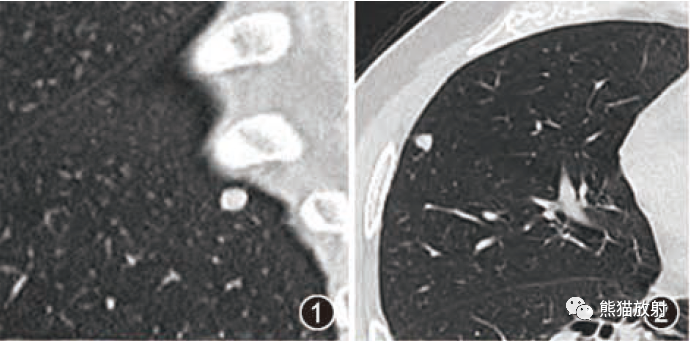

下图2例GGO,左侧无纤维化,可治疗;右侧伴牵引性支气管扩张,提示纤维化,不可治愈。